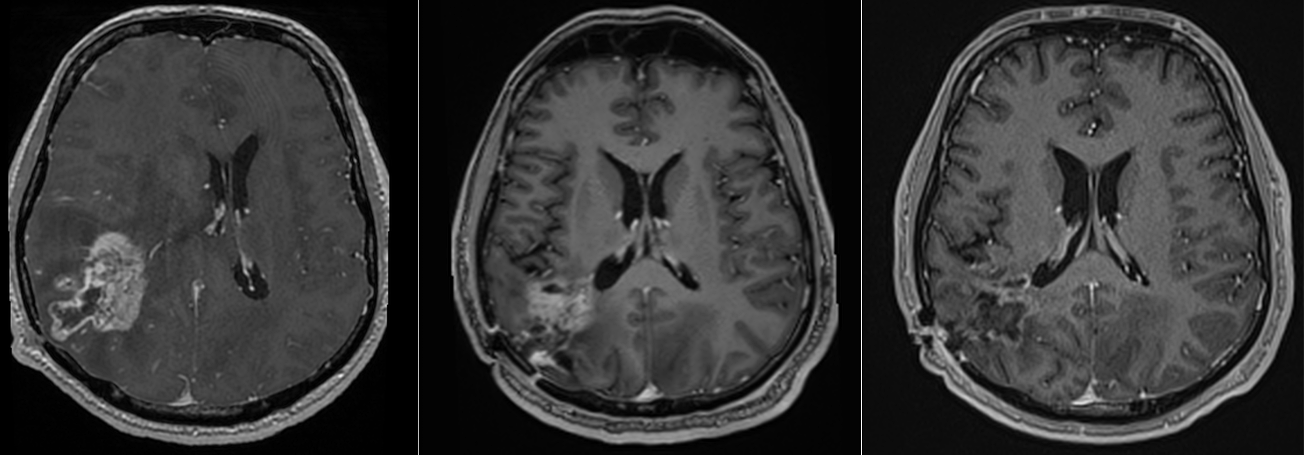

La nivel imagistic, glioblastomul apare adesea ca o leziune relativ bine delimitată, cu captare inelară de contrast și necroză centrală. Pentru ochiul neavizat, aceasta poate sugera o tumoră care ar putea fi „scoasă complet”. În realitate, ceea ce vedem pe RMN reprezintă doar componenta cea mai densă tumoral.

La nivel microscopic, celulele tumorale:

- migrează de-a lungul tracturilor de substanță albă

- infiltrează cortexul aparent normal

- utilizează spațiile perivasculare ca „autostrăzi biologice”

Studii histologice au arătat că aceste celule pot fi prezente la centimetri distanță de leziunea vizibilă. Astfel, chiar și o rezecție chirurgicală extinsă lasă inevitabil în urmă un substrat tumoral microscopic.

Această realitate transformă glioblastomul dintr-o boală locală într-una sistemică, la nivelul creierului.

Imagistica – instrument esențial, dar imperfect

RMN-ul cerebral este standardul diagnostic, dar trebuie interpretat în context.